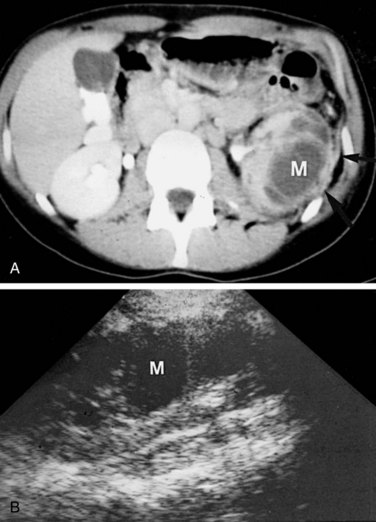

These studies are commonly used to evaluate patients initially for complicated UTIs or factors or to reevaluate patients who do not respond after 72 hours of therapy (see later). Ultrasonography (Fig. 10–19) and CT show renal enlargement, hypoechoic or attenuated parenchyma, and a compressed collecting system. They also may delineate focal bacterial nephritis and obstruction. When parenchymal destruction becomes pronounced, a more disorganized parenchyma and abscess formation associated with complicated renal and perirenal infections may be identified (Soulen et al, 1989).

Figure 10–19 Acute pyelonephritis. Ultrasound image of the right kidney demonstrates renal enlargement, hypoechoic parenchyma, and compressed central collecting complex (arrows).

(From Schaeffer AJ. Urinary tract infections. In: Gillenwater JY et al, editors. Adult and pediatric urology. Philadelphia: Lippincott William & Wilkins; 2002. p. 211–72.)

Ultrasonography and CT establish the diagnosis. On ultrasonography the lesion is typically poorly marginated and relatively sonolucent with occasional low-amplitude echoes that disrupt the cortical medullary junction (Corriere and Sandler, 1982) (Fig. 10–21A). Enhancement with a contrast agent is necessary with CT studies because the lesion is difficult to visualize on the unenhanced study (see Fig. 10–21B). Wedge-shaped areas of decreased enhancement are seen. No definite wall is evident, and frank liquefaction is absent. Conversely, abscesses tend to have liquid centers, are usually round, and are present both before and after contrast medium enhancement. More chronic abscesses may also show a ring-shaped area of increased enhancement surrounding the lesion (Corriere and Sandler, 1982). Gallium scanning reveals uptake that is in the region of and larger than the previously demonstrated mass (Rosenfield et al, 1979). In patients with multifocal disease the findings are similar but multiple lobes are involved.

Figure 10–21 Acute focal bacterial nephritis. A, Ultrasound image: longitudinal view of the left kidney demonstrates spleen (S) and left kidney (arrows). Note irregular midpole mass (M) of slightly higher echo texture than surrounding normal renal parenchyma. B, Contrast medium–enhanced CT scan demonstrates a wedge-shaped area of low density (arrows) in the middle portion of the left kidney. The findings resolved after antimicrobial therapy.

(From Schaeffer AJ. Urinary tract infections. In: Gillenwater JY et al, editors. Adult and pediatric urology. Philadelphia: Lippincott Williams & Wilkins; 2002. p. 211–72.)